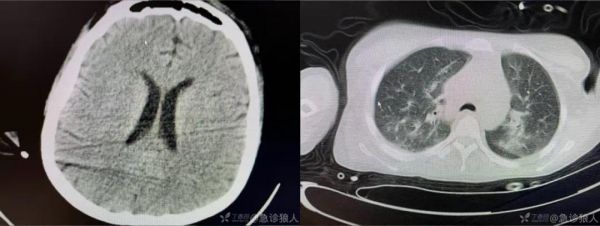

CT:

肝内外胆管都没见明显的胆管扩张,从转氨酶上看患者存在明显的肝细胞性损伤。肝脏在 CT 上密度下降。